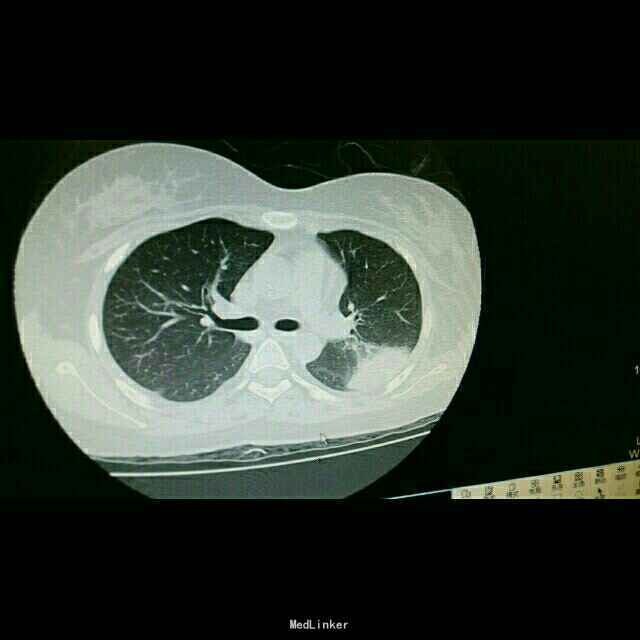

主诉:发热15天 病史:患者因视神经脊髓炎在我院神经内科住院,予以激素治疗。后因发热转我科。

查体:双肺湿罗音,余无特殊。 辅查:9.10胸部CT双肺炎症。10.2原炎症部位出现空洞。10,21原炎症部位好转,空洞无明显变化。

诊断:肺曲霉病。 治疗:开始予以伏立康唑治疗,仍有发热,后予以两性霉素*B治疗。